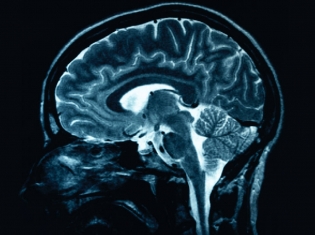

Brain scans, like positron emission topography (PET) and magnetic resonance imaging (MRI), have also been used to look for signs of plaques and tangles in the brain.